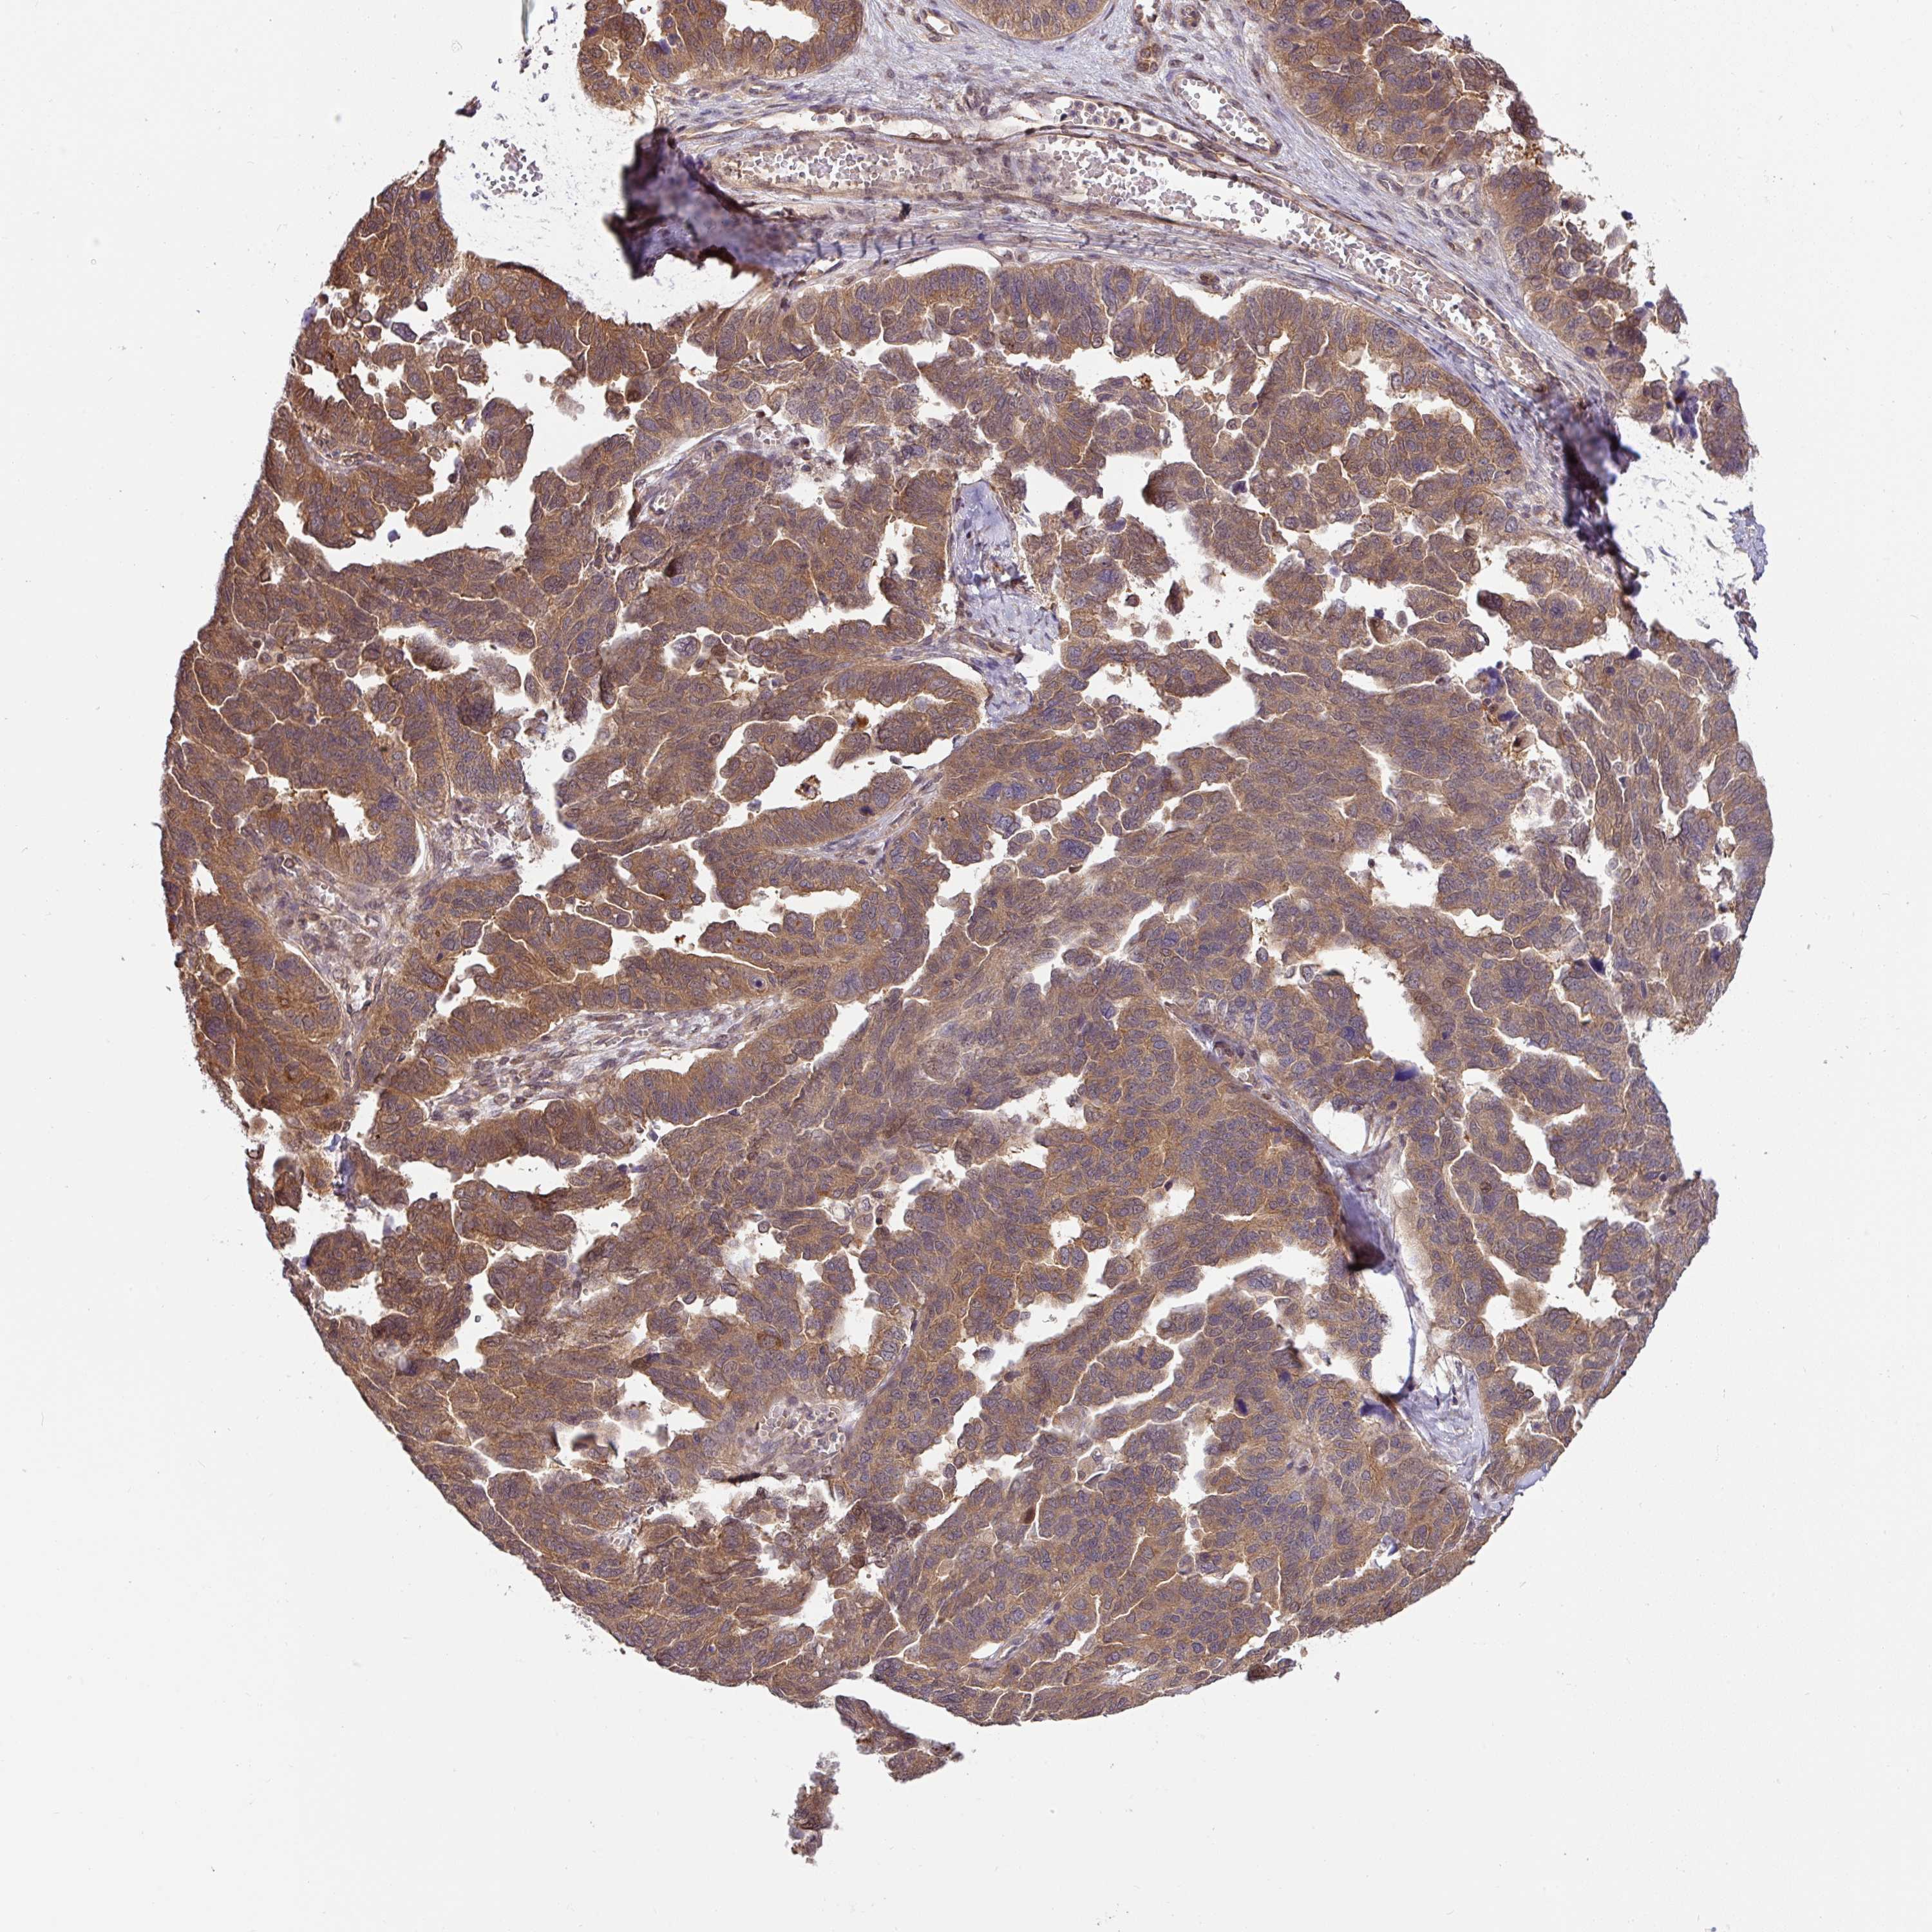

OVARIAN CANCER - Protein expressioni

A mouse-over function shows sample information and annotation data. Click on an image to view it in a full screen mode. Samples can be filtered based on level of antibody staining by selecting one or several of the following categories: high, medium, low and not detected. The assay and annotation is described here.

Note that samples used for immunohistochemistry by the Human Protein Atlas do not correspond to samples in the TCGA dataset.

Antibody stainingi

Antibody staining in the annotated cell types in the current human tissue is reported as not detected, low, medium, or high, based on conventional immunohistochemistry profiling in selected tissues. This score is based on the combination of the staining intensity and fraction of stained cells.

Each image is clickable and will lead to virtual microscopy that enables deeper exploration of all samples and also displays staining intensity scores, fraction scores and subcellular localization as well as patient and tissue information for each sample.

Antibody HPA049911

Antibody CAB010161

Cystadenocarcinoma, serous, NOS

Cystadenocarcinoma, mucinous, NOS

Adenocarcinoma, NOS

Carcinoma, endometroid

Carcinoma, NOS